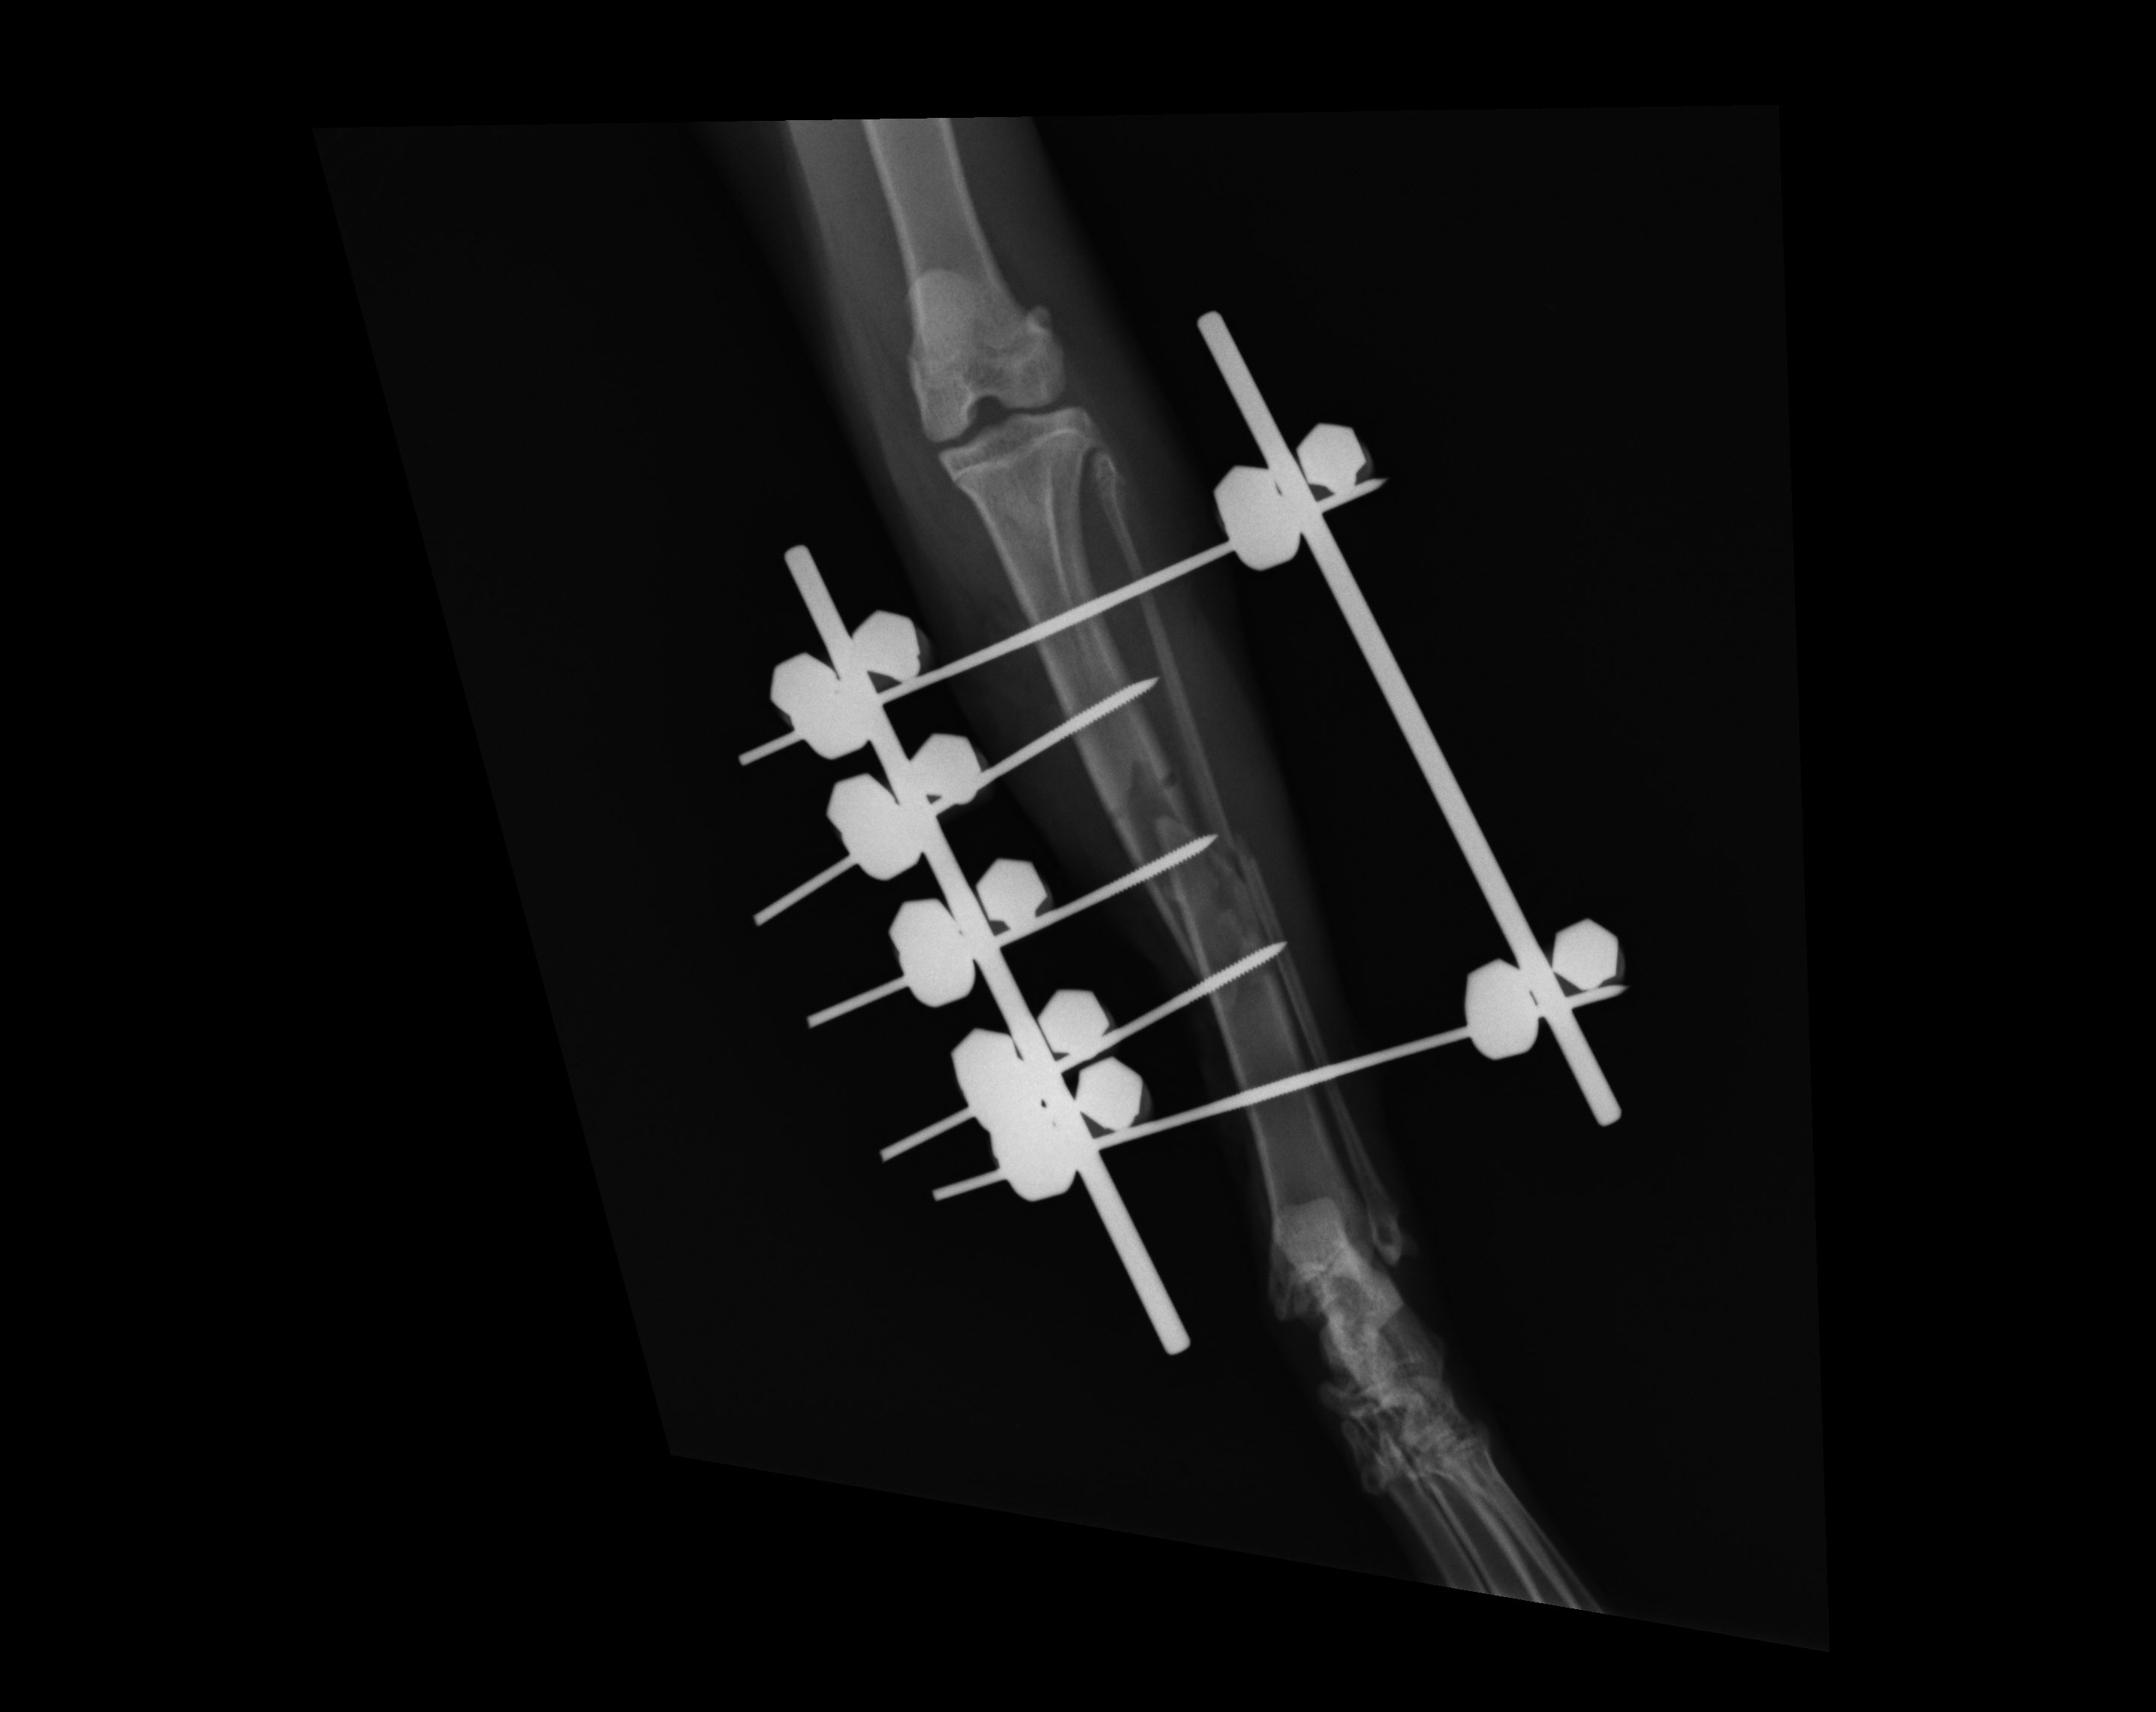

IMEX SK™ Linear ESF System

The SK™ ESF System features dramatically improved connecting rods that make use of simpler frames a clinical reality. The by-products of simple frame constructs include: economy of hardware, reduced operative time, and less required instrumentation. The SK™ ESF System is available in three sizes; mini, small, and large suitable for cats and toy dogs, up to the large size for heavier dogs.